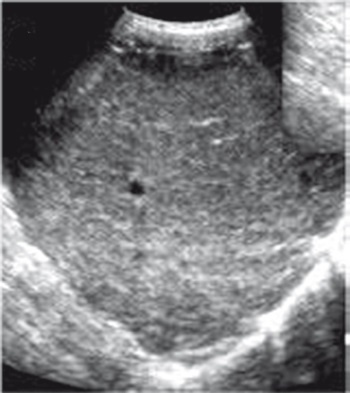

УЗИ имеет преимущества при скрининговой диагностике НАЖБП, особенно у пациентов без клинических симптомов поражения печени. При УЗИ печени определяется;

✓ диффузная гиперэхогенность паренхимы печени и неоднородность ее структуры;

✓ нечеткость и/или подчеркнутость сосудистого рисунка;

✓ дистальное затухание ЭХО-сигнала.

Иллюстрация к книге — Неалкогольная жировая болезнь печени [i_038.jpg]

Рис. 35. Эхограмма печени при НАЖБП